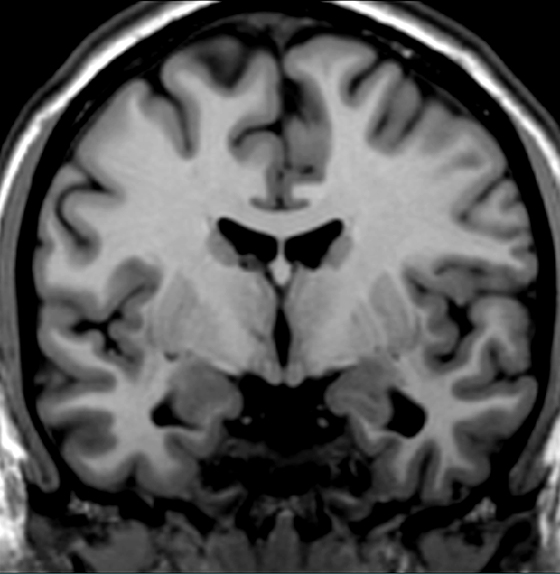

Locate a major pathway (bundle of axons) that originates from the hippocampus.